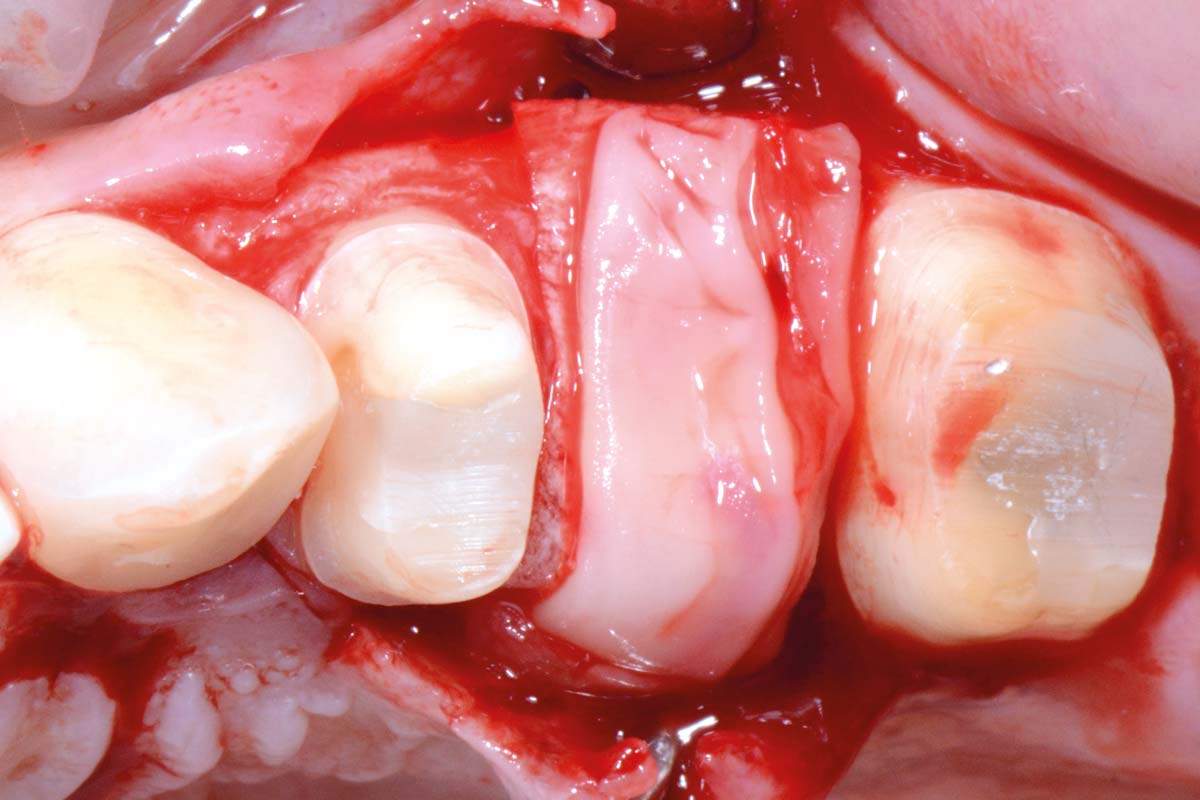

03/16 - Jason® membrane placed as palatal “wall” supporting the allogenic granules (maxgraft®)Full bone regeneration in extraction socket augmented with maxgraft® and Jason® membrane – Dr. C. Landsberg